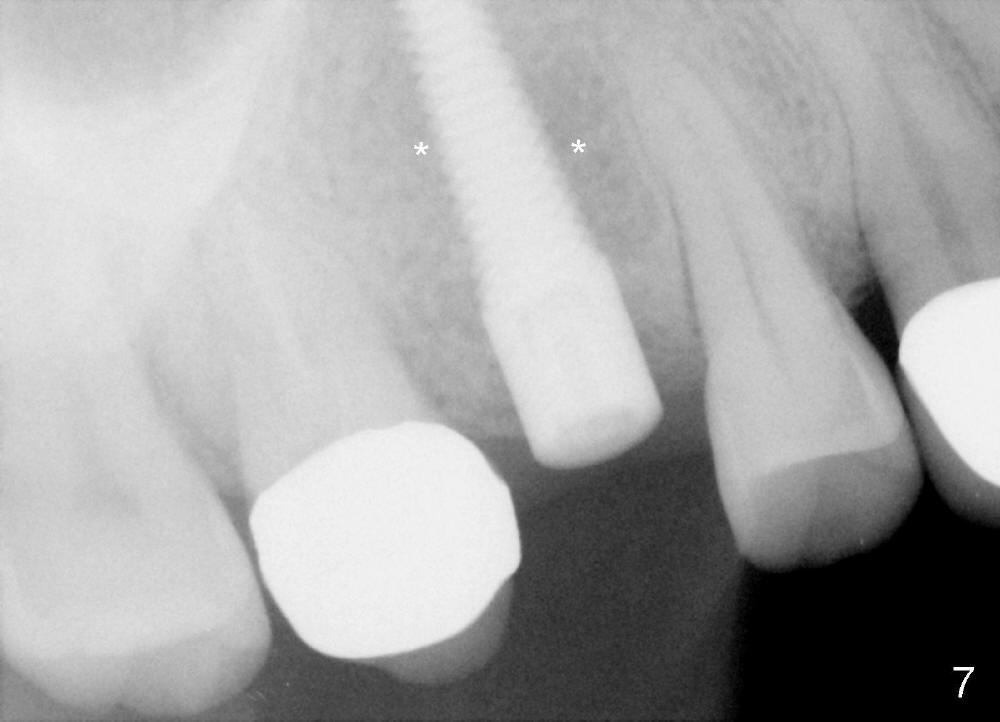

Mrs. Zhao, in her late forties, is apprehensive of dentistry. She has postponed implant placement for #4 for two months (Fig.1,2). Immediate implant is planned. Immediate provisional is provided if insertion torque is more than 45 Ncm. There are two conditions which are unfavorable to immediate provisional. First, she is probably a bruxer, as indicated by torus palatinus (Fig.1 *). Second, she bit off two crowns (joined) for #3 and 4 together.